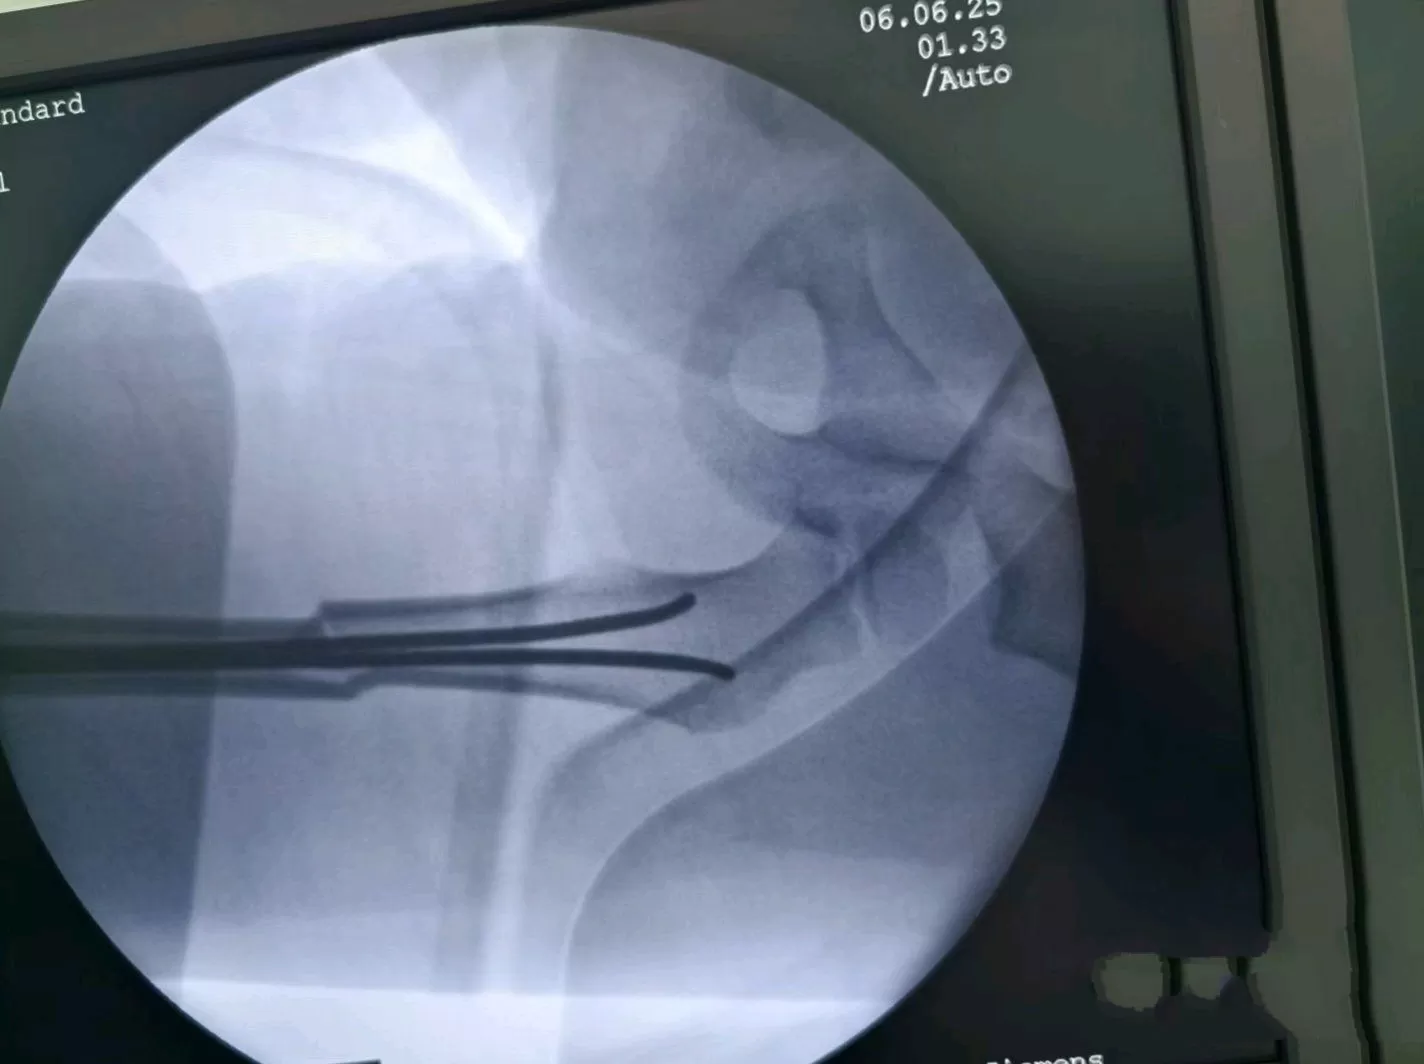

At 4:40 p.m. that day, Lele was wheeled into the operating room. Dr. Chou Xiaobing’s team was already prepared—this "precision reduction with elastic intramedullary nails" is their signature technique. Over the past decade, it has been used in over 4,000 surgeries, compressing the time for complex pediatric fracture procedures to 30 minutes with an error margin controlled within 1 millimeter.

While Ms. Li clutched her husband’s hand, trembling outside the operating room, real-time monitoring on the screen showed that intraoperative radiation exposure was 70% lower than in traditional surgeries—a low-dose imaging method unique to children’s hospitals. The two incisions, each smaller than 2 centimeters, barely bled—this is the "bloodless surgical field" standard of the Pediatric Orthopedics Department at Jingdu Children’s Hospital. At 5:30 p.m., Dr. Chou walked out of the operating room: "The bone is aligned perfectly. The child can take a sip of water once he wakes up."